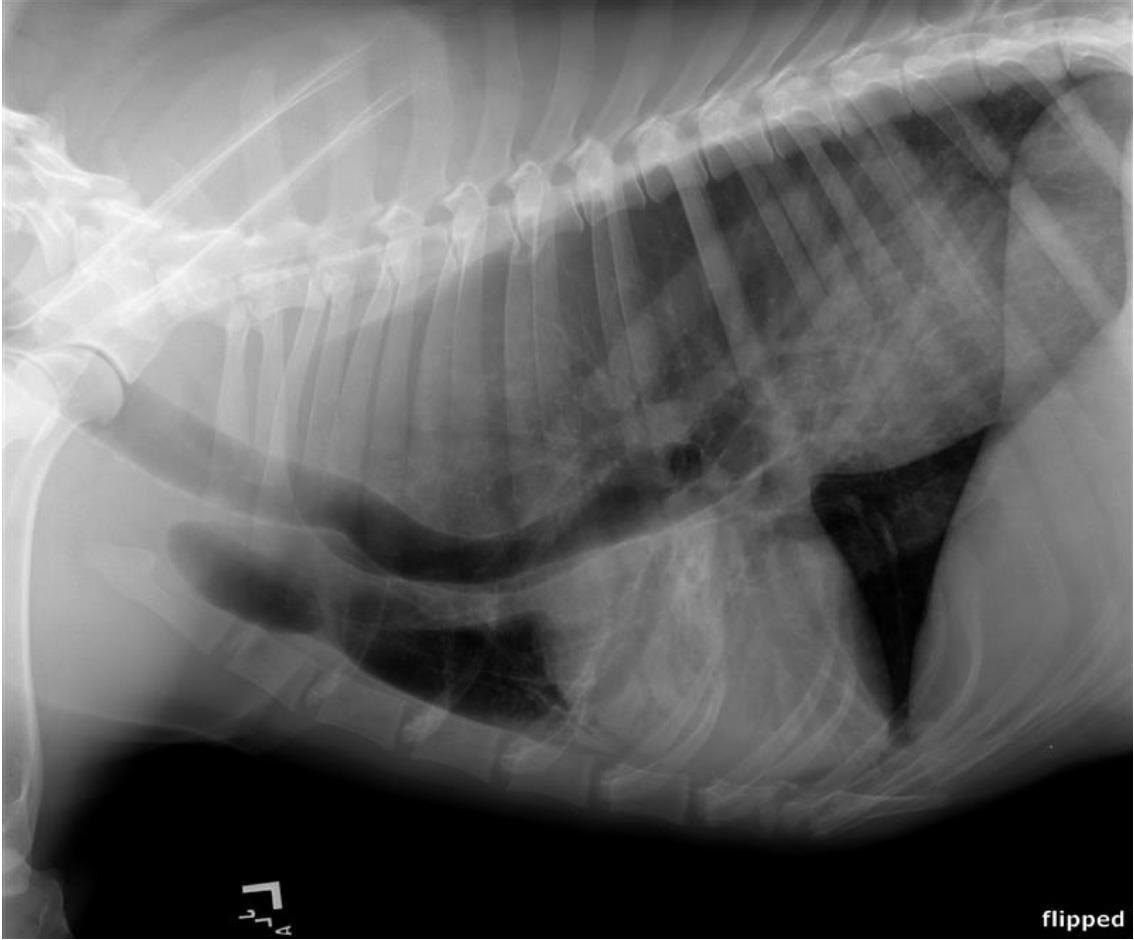

• You’re working in a small animal practice. A 6-year-old German Shepherd male is presented due to ongoing vomiting and coughing over the last month particularly after meals. His owner reported that Max had been regurgitating undigested food shortly after eating, sometimes accompanied by coughing and retching. On clinical examination, rectal temperature, heart rate and respiratory rate were found within normal limits. You obtain thoracic radiographs, what is the most likely diagnosis?

megaoesophagus